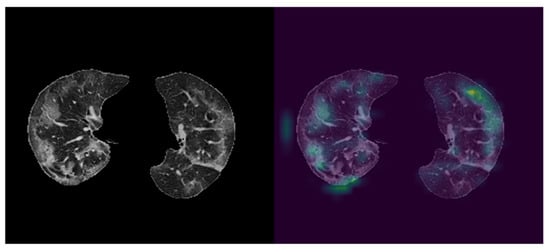

CNN blocks of the proposed network were utilized to obtain feature maps of ground glass opacities (GGO). To illustrate the effectiveness of the approach used in this study, the last class activation map (CAM) was visualized with the help of Grad-CAM (Figure 5). As it can be seen from Figure 5, features were primarily extracted from ground glass opacities.

We further evaluated Grad-CAM consistency by calculating the effect of different perturbations. We compared four perturbed states: clockwise rotated, counterclockwise rotated, 30 pixels x-axes and −15 pixels y-axes translated, and −20 pixels x-axes and 15 pixels y-axes translated (see Figure S1). We used cosine similarity (CS) to measure the effect of perturbations applied on the feature map of the original image ( O p ) and the perturbed one ( P ) (see Supplementary Materials for the Equation). The average similarity between the feature map of the original image and the feature maps of the perturbed images was 0.98. The two vectorized maps are similar when CS is close to 1; therefore, calculated similarity indicates Grad-CAM consistency.

The following are available online at https://www.mdpi.com/article/10.3390/ai2030020/s1, Figure S1: Illustration of the original CT slices (left) and activation maps (right) of the original (A) and the perturbed images (B-E) based on Grad-CAM.

Figure 5. Visualization of CNN outputs. left: Cropped CT image, right: visualized feature map of CNN output. The right image shows CNN blocks are capable of capturing Ground Glass Opacities in CT images.